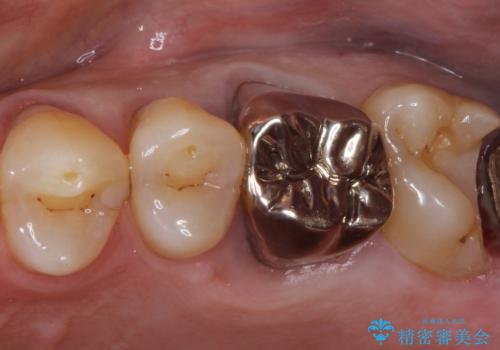

ゴールドインレーによる修復治療

- 他院で入れた銀の詰め物が取れたことを主訴に来院されました。

内部の虫歯を除去し、ゴールドインレーにて修復治療を行っております。

ゴールドインレーは適合が良く、割れることもないため、長期的に安定した治療法となります。